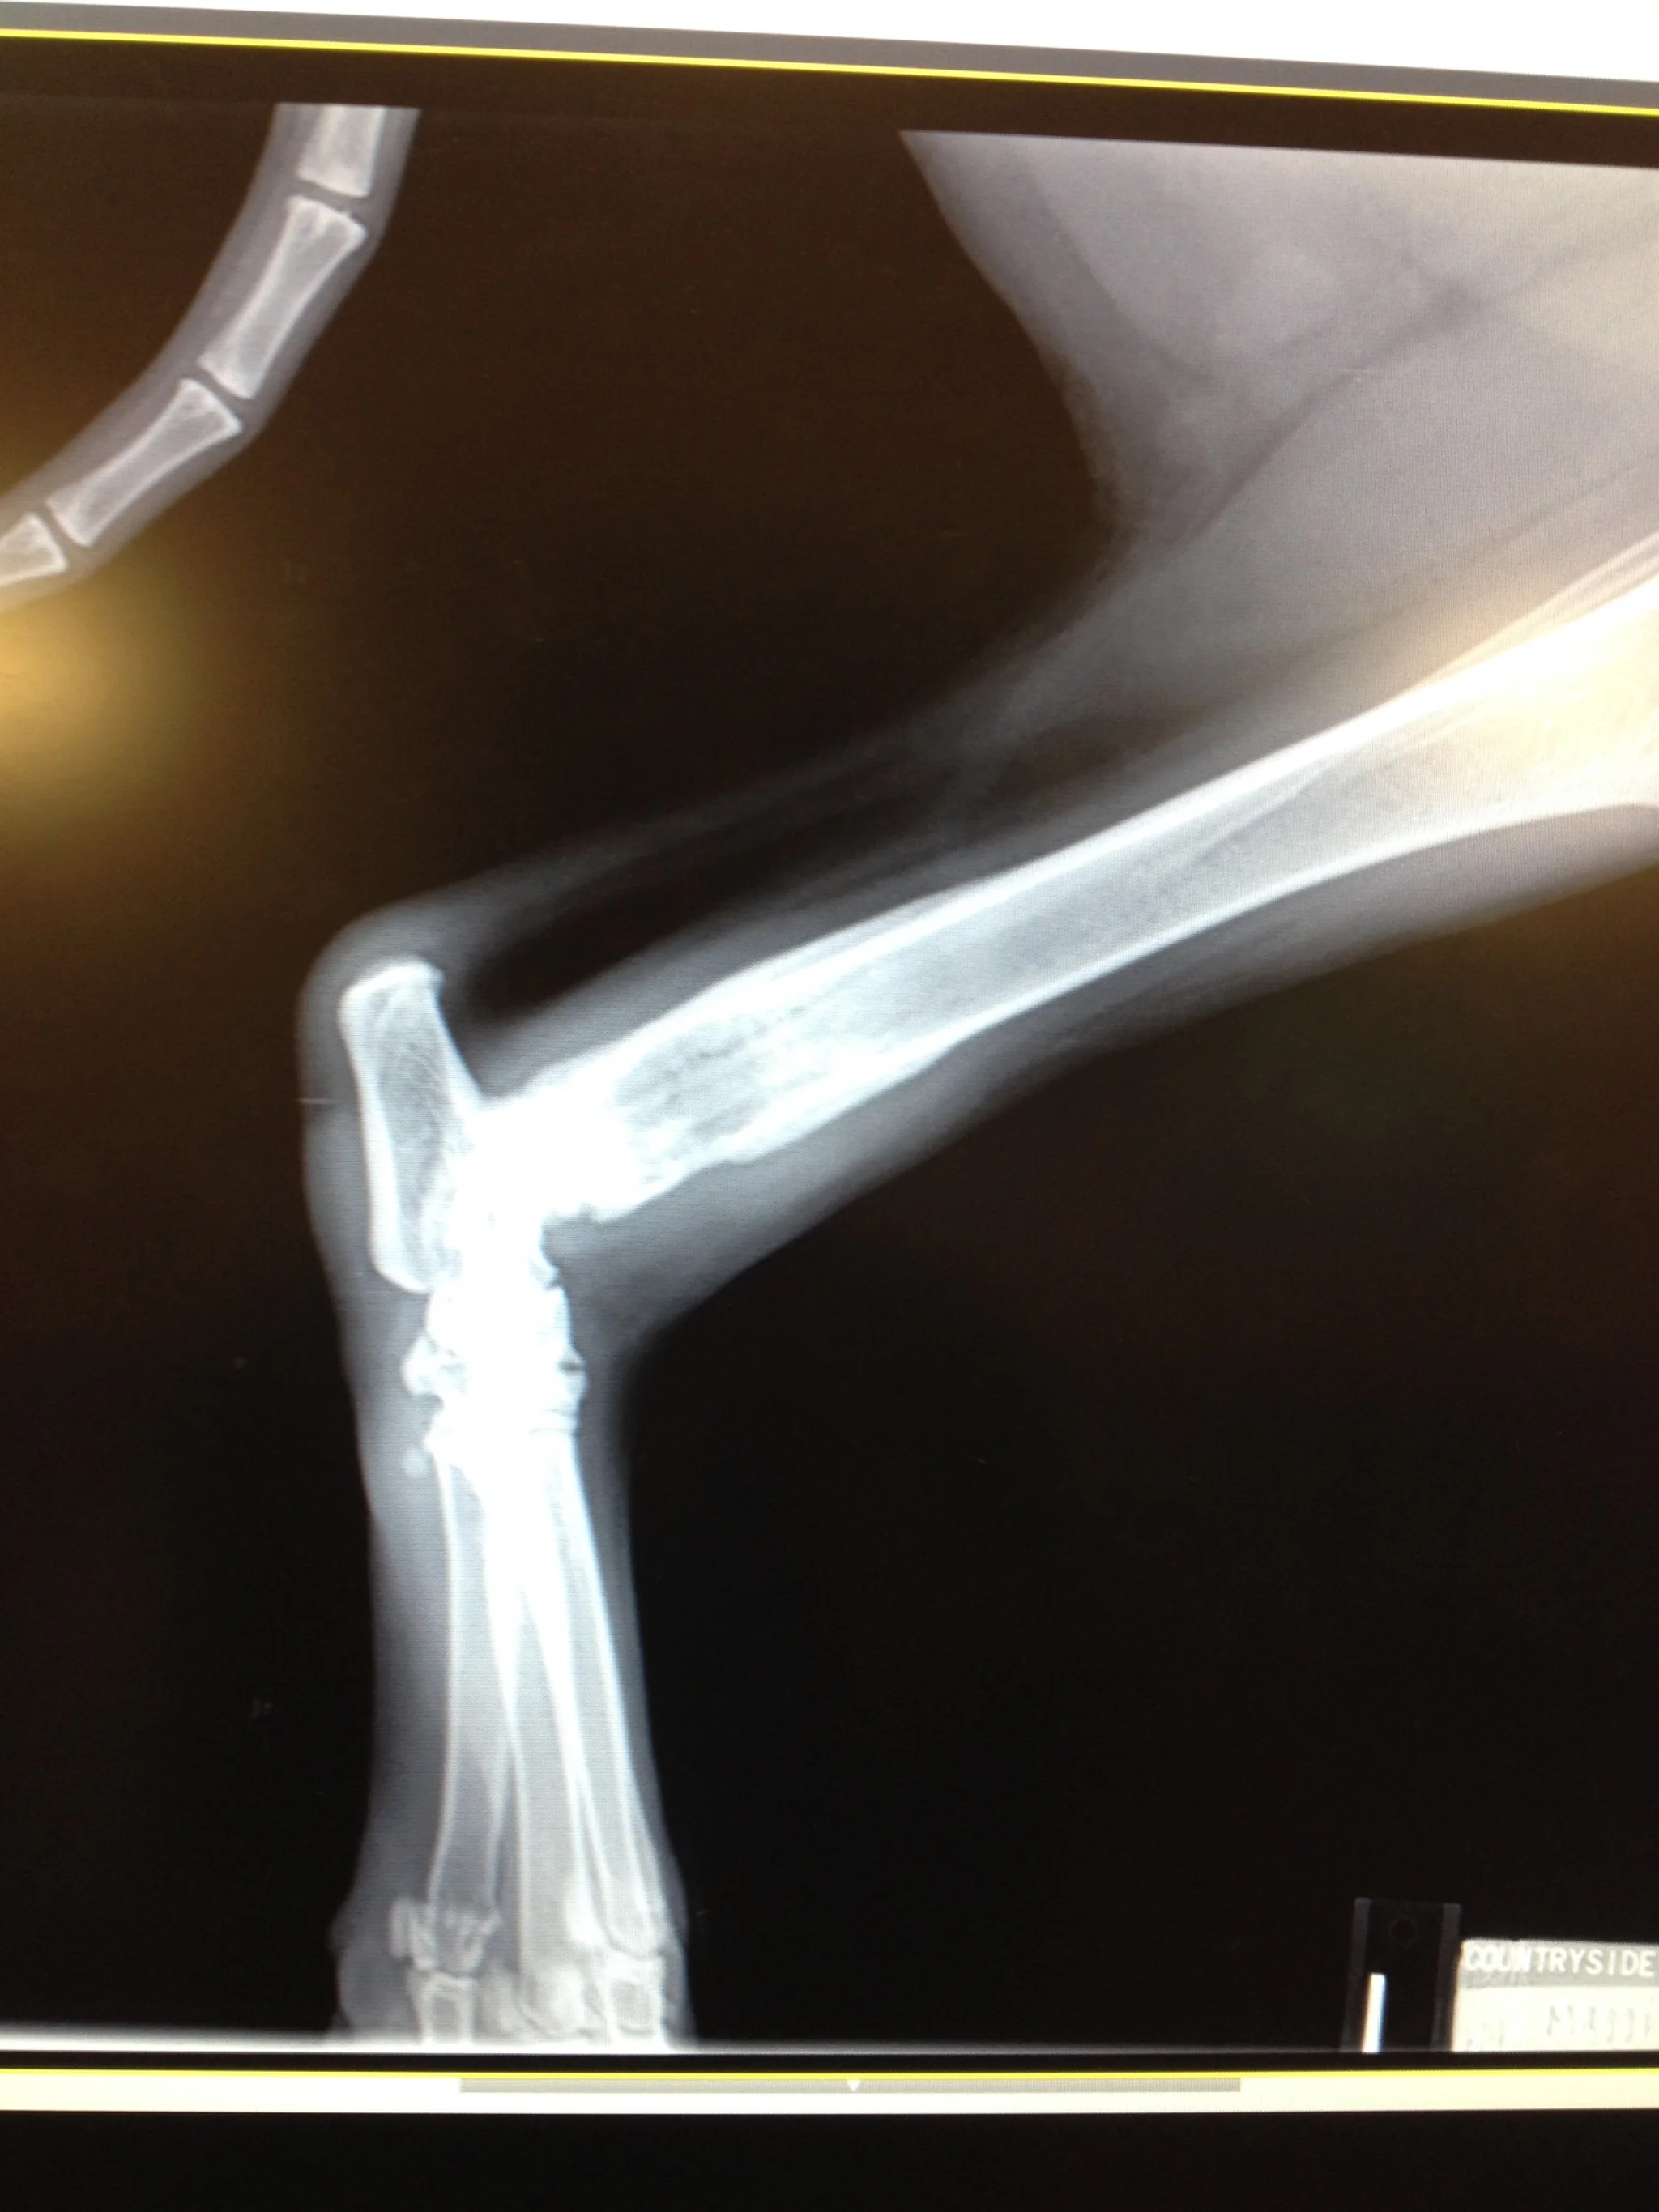

There's a spot on the leg, right above the joint there that's swollen and a little brighter. That spot is a very bad sign.

One biopsy later, and the vet told us: It's osteo sarcoma. A bone cancer that advances rapidly, and metastasizes readily into the lungs and other parts of the body. Left untreated, that swelling will increase, and soon weaken the bone to the point where a very painful fracture is likely. And that's if the cancer doesn't spread to other areas faster than the bone weakens.